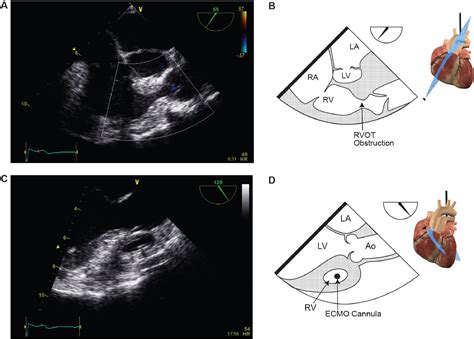

Cardiomyopathy

Outflow tracts on ultrasound are also important in the evaluation of cardiomyopathies, particularly hypertrophic cardiomyopathy. Ultrasound can detect left ventricular hypertrophy, dynamic outflow tract obstruction, and systolic anterior motion of the mitral valve, aiding in the diagnosis and management of this condition.

Post-Operative Evaluation

Ultrasound is widely used for post-operative evaluation of patients who have undergone cardiac surgery. It helps in assessing the function of prosthetic valves, detecting complications such as paravalvular leaks, and monitoring the healing process.